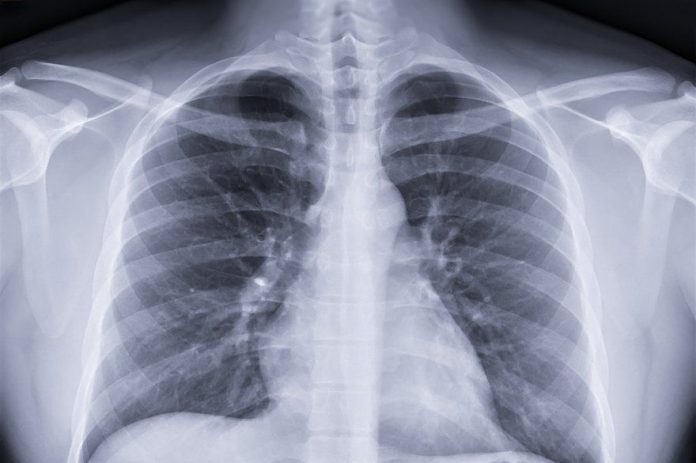

Recently, the British Standards Institution (BSI) officially approved Infer Vision’s TB UKCA certification, which is the first TB UKCA certification approved for a Chinese AI medical company. As of July 2023, Infer Vision is the first and only Chinese AI medical technology company in the world whose products have received regulatory approvals in the five major markets of China, the US, the EU, the UK, and Japan, gaining access to the vast majority of the world’s major healthcare markets, and with its products covering over 1,000 healthcare organizations in more than 20 countries around the world.

Less than two weeks ago, Infer Vision’s DR Chest Disease Assisted Screening product officially passed the MDR CE certification, which, up to now, is the first MDR CE certification passed by a Chinese AI healthcare company globally that focuses on TB screening and diagnosis. Together with Infer Vision’s current UKCA certification for its TB AI products, Infer Vision’s TB AI products have now received dual certification from the EU’s MDR CE and the UK’s UKCA.

As medical products are related to human life and health, they are subject to extremely stringent regulatory measures in all countries around the world, and the AI medical industry is also characterized by a high barrier to entry. UKCA (UK Conformity Assessment) is a product certification system launched by the UK government to ensure that products sold in the UK market comply with the relevant technical standards and requirements. The UK is considered one of the major markets for medical devices globally due to its highly developed healthcare system, innovative R&D environment, international cooperation and exports, as well as government support and regulation, which makes the UK an important market for attracting both domestic and foreign manufacturers and suppliers of medical devices, and occupies an important position in the global medical device market.

From 2021, the UK officially leaves the European Union and exits the European Single Market and Customs Union. As a result, for products planned to be sold in the UK market, they need to comply with the new UK market access requirements, and UKCA certification has become a necessary condition for legally selling products in the UK market. By taking the lead in obtaining UKCA certification for tuberculosis products, presumptive has already grabbed a head start in the UK market, laying a solid foundation for the subsequent commercialization process.

Not only the UKCA certification in the UK market, Infer Vision has previously been successfully included in the commercial service catalog of the National Healthcare System in the UK, and has established offices in both London and Birmingham to further penetrate into the UK and other overseas markets.

As early as 2021, Infer Vision’s self-developed InferRead CT Lung was included in the UK’s NHS Shared Commercial Services (NHS SBS) framework, providing early screening testing services for lung nodules for UK patients and helping the NHS to reduce the cost of lung cancer prevention and treatment.In May 2023, Infer Vision’s AI solution was once again selected for the NHS SBS framework. The successive renewals of NHS SBS are of great significance to Infer Vision, not only does it mean that the solution is recognized and affirmed by the NHS, but also that our services and deployment capabilities have stood the test of the international market.

In 2020, Infer Vision’s AI-assisted diagnostic products have been awarded the EU CE, US FDA, Japan PMDA, China NMPA, and UKCA medical device registration certificates, making Infer Vision the world’s first, and still the only, Chinese AI medical technology company to have received regulatory approval from all five healthcare markets and authoritative organizations, officially opening the “Five Certificates in One” process. Opening the “five certificates complete” era, prying the global AI medical market! Behind this is a huge investment in research and development, which is also the best proof of the ability of Nano’s products. Infer Vision’s “five certificates” cover the world’s most important markets with the highest level of medical care and the most stringent access audits, and also provide an important reference for market access in other countries and regions around the world.

Infer Vision has always been the main force in the internationalization of China’s AI medical enterprises, and since the successive establishment of Infer Vision’s Japanese, North American, and European teams in 2018, its products have been widely acclaimed in the international arena. What’s more, Infer Vision is one of the few AI medical companies that have business teams overseas and really carry out international cooperation, and it has continued to make new progress and good news in product registration, overseas commercialization, and international standard development.